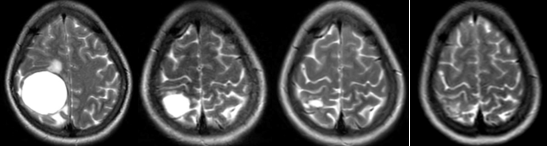

Sau đó, bệnh nhân tiếp tục duy trì điều trị với osimertinib đến thời điểm đánh giá lại tháng 9 năm 2024, sau gần 2 năm điều trị, bệnh nhân vẫn đáp ứng rất tốt, không đau ngực, không khó thở, chỉ điểm khối u CEA và Cyfra 21-1 duy trì ở mức bình thường. Hình ảnh u phổi trên phim cắt lớp vi tính không thay đổi nhiều song trên phim cộng hưởng từ, kích thước khối u giảm đáng kể.

Hình 5: Hình ảnh khối u não trên phim cộng hưởng từ qua các mốc thời gian 10/2022, 6/2023, 6/2024 và 9/2024.